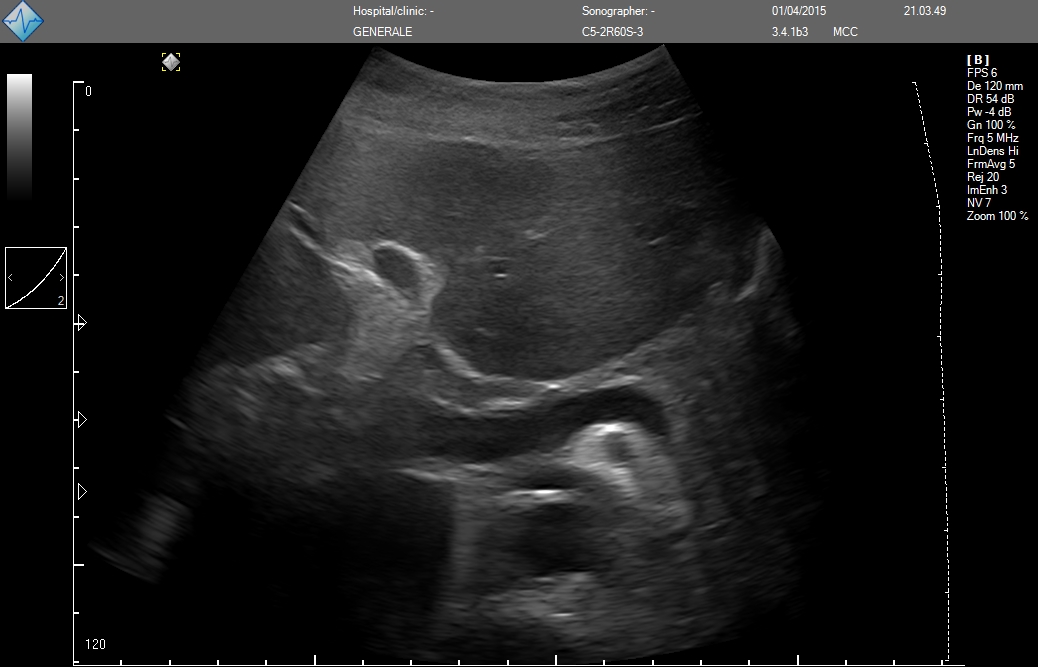

Исследование FAST (Сфокусированная сонографическая оценка при травме) позволяет выявить наличие жидкости в предполагаемых клинических условиях, визуализируя 10 структур или пространств в четырех областях:

- Околопеченочной

E-FAST (расширенный-FAST) дополнительно обследует переднюю и боковую плевральную полость (торакальная проекция) для оценки наличия пневмоторакса или плеврального выпота, предположительно гемоторакса у пациентов с травмой.